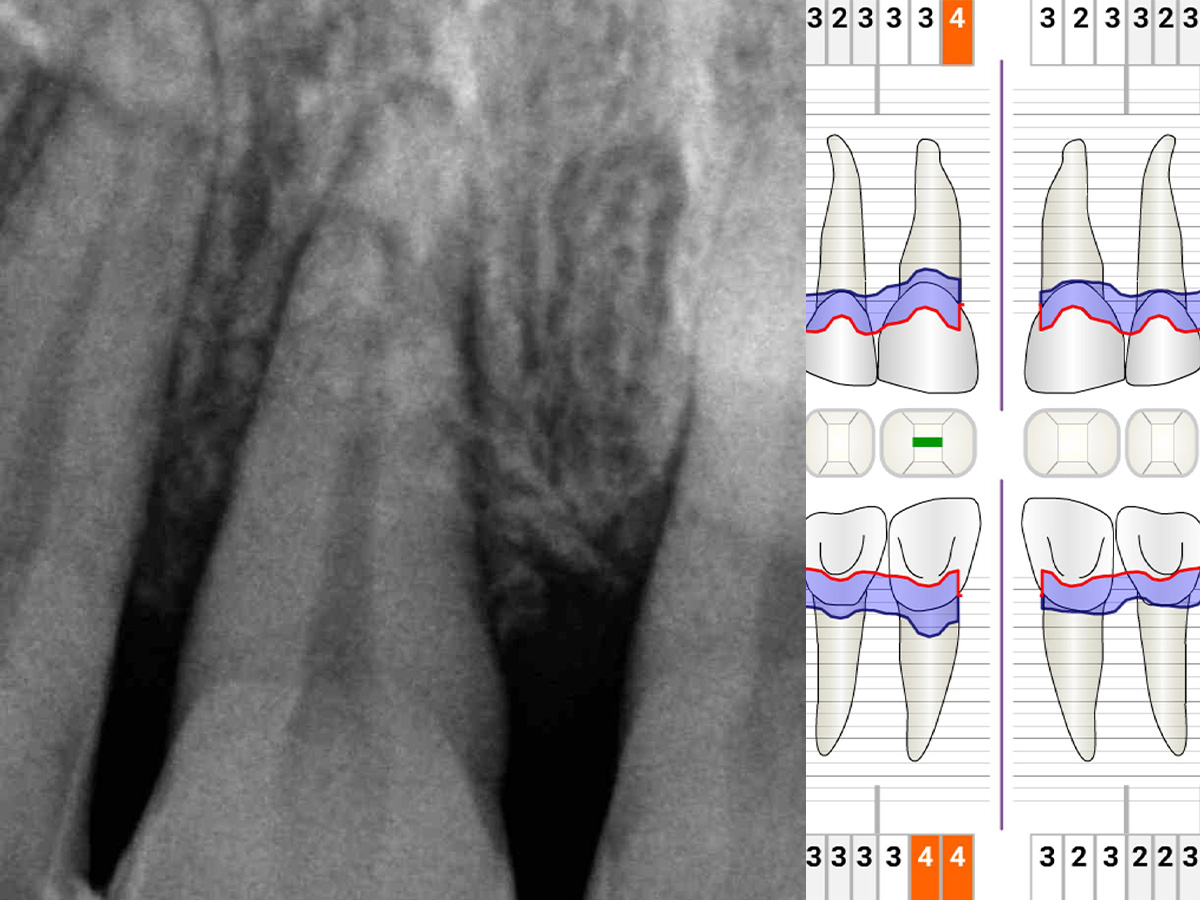

Während der intraoralen Untersuchung wurden eine erhöhte Beweglichkeit sowie erhöhte Taschensondierungstiefen und klinische Entzündungszeichen an Zahn 11 festgestellt. Ein intraorales Röntgenbild wurde angefertigt. Die intraossäre Defektkomponente gemeinsam mit dem hohen Niveau an Mundhygiene bieten eine gute Grundlage für einen regenerativ-parodontalchirurgischen Eingriff. Zehn Tage vor dem Eingriff wurde der Zahn mit dem Nachbarzahn verblockt und ein lokales Antibiotikum in die parodontale Tasche appliziert, um zum Zeitpunkt des Eingriffs möglichst entzündungsarme Verhältnisse vorzufinden. Unmittelbar vor Beginn des chirurgischen Eingriffs wurde der Defektboden mit einer Parodontalsonde ausgelotet, um Informationen über die dreidimensionale Defektmorphologie zu erhalten (Abb. 1-3).

Abbildung 1

Abbildung 2

Abbildung 3